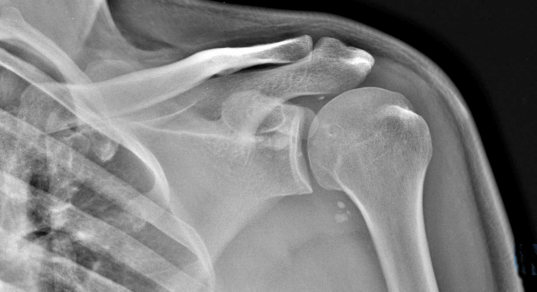

По данным рентгенографии: нестабильность остеосинтеза левой плечевой кости пластиной, диастаз (щель) между отломками.

Снимок через 3 года после травмы: полное сращение плечевой кости и перестройка трансплантата из гребня подвздошной кости

Характерный признак псевдоартроза - подвижность сустава там, где в норме ее быть не должно. На рентгенограмме отчетливо прослеживается увеличение суставной щели и отсутствие костной мозоли.